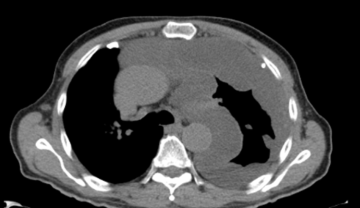

Healthy lung compared to mesothelioma

CT Scan

A CT scan is commonly used to help diagnose mesothelioma by providing detailed images of the chest or abdomen.